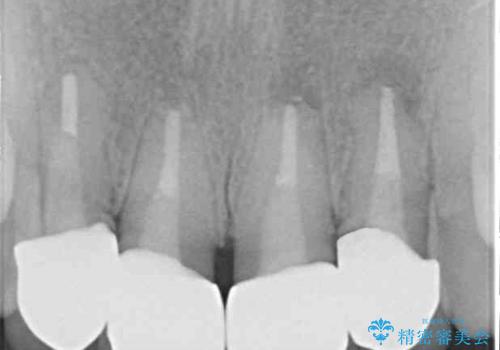

根尖病変が原因で、膿が出てきている歯があったため、仮歯を置き換える際に根管治療を行うこととしました。

仮歯を変えたことで歯肉の腫れは引き、根管治療も功を奏して膿の出口はきれいに消退しました。